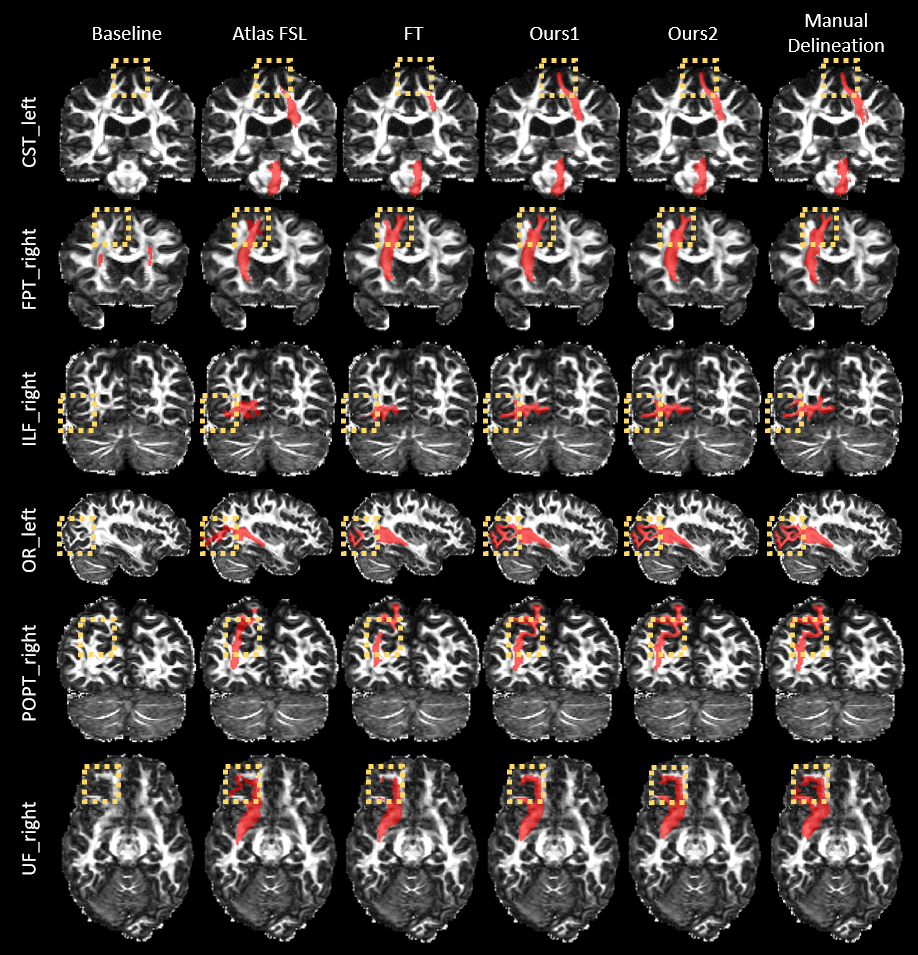

We first evaluated the accuracy of the proposed method, where the segmentation model for existing WM tracts was fine-tuned with the annotations of novel WM tracts using either the initialization strategy proposed in Sect. 2.2 or the more convenient implementation in Sect. 2.3. These two approaches are referred to as Ours1 and Ours2, respectively. We compared our methodology with three competing methods. The first one is the baseline TractSeg network that was trained from scratch with the annotations of novel WM tracts. The second one is a representative conventional registration-based method Atlas FSL described in [17], where an atlas is created from the available annotated scans and registered to test scans for segmentation. The third one is the classic fine-tuning method based on the segmentation model for existing WM tracts, which is referred to as FT.

The proposed method was first evaluated qualitatively. Cross-sectional views of the segmentation results for representative test subjects and novel WM tracts are shown in Fig. 1. The manual delineations are also shown for reference. It can be seen that the results of both of our strategies better resemble the manual delineations than the competing methods.